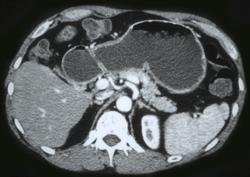

Linitis Plastica